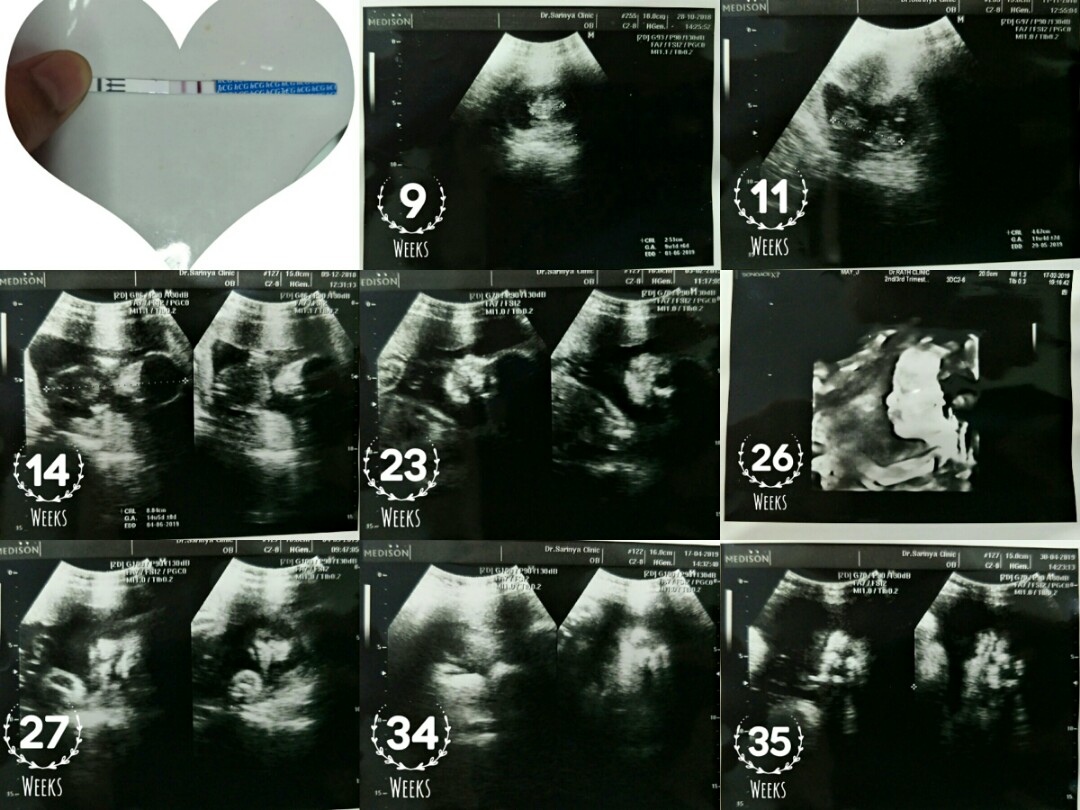

กี่สัปดาจร้า สามารถซาวเจอลูกในท้อง ท้องเเรกจร้า

บ้านนี้9wค่ะ

บ้านนี้8w5dคะ

8สัปดาห์ค่ะ

บ้านนี้8w

6วีคค่ะ

8วีคค่ะ

6 weekค๊า

6 wks ค่ะ